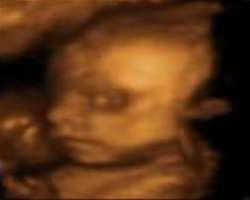

- ecografia 4D ajuta in reprezentarea imaginii ecografice spaţială a formelor aflate în volumul examinat ecografic, în timp real.

- 4D reprezinta patru dimensiuni: lungime, înălţime,lăţime si timp.

- ecografia fetală 4D ne prezinta imaginea corpului fătului aflat în uter cu mişcările pe care le are în momentul examinării.